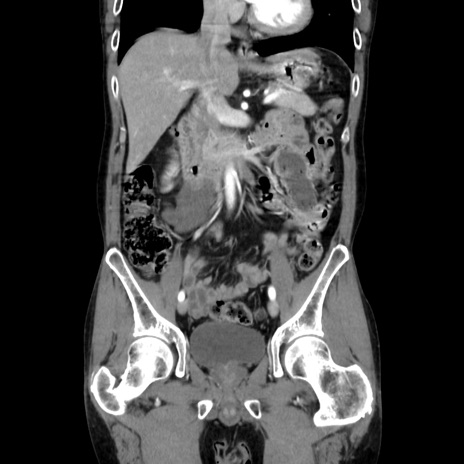

症例37(冠状断像)

【症例】40歳代 男性

【主訴】腹痛

【現病歴】4時間ほど前に電車に乗車中に臍部上より腹痛出現。徐々に増悪し起立困難となり、救急外来受診。生ものは数日食べていない。今朝お雑煮を食べた。

【身体所見】BT 36.8℃、BP 117/84mmHg、HR 91/min、SpO2 97%、苦悶様、腹部:臍上部広範囲圧痛あり、反跳痛±

【データ】WBC 8100、CRP 0.03